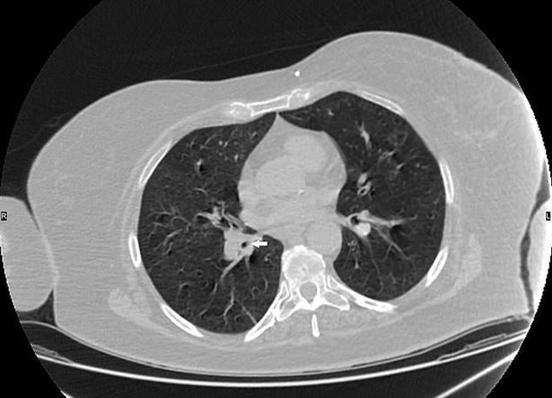

她被立刻送去接受X光检查 , 但医生无法看到断裂的拭子在哪里 , 只能发现她的右肺部有些肿胀 。 于是 , 医生们决定将一个微型摄像头伸入到她的肺中 , 以帮助找到拭子的具体位置 , 再使用设备进行手术将其取出 。